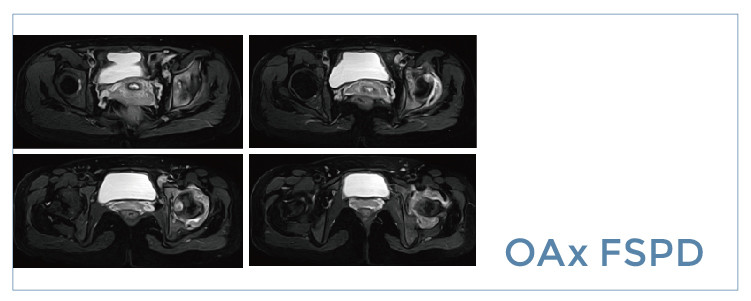

【朗润影像档案】磁共振影像病例分享(编号20190809)